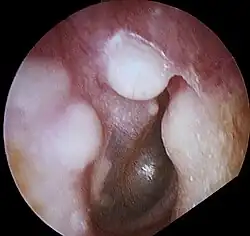

présence d'exostose dans le conduit auditif externe droit